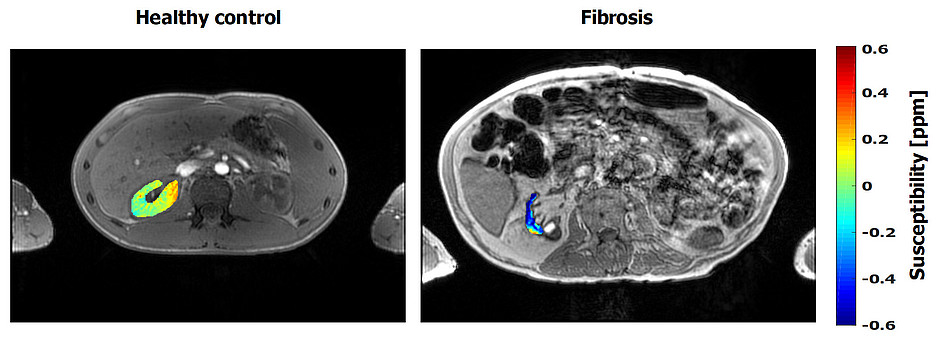

Quantitative Suszeptibilitätskartierung (QSM)

Die quantitative Suszeptibilitätskartierung (engl: quantitative susceptibility mapping, QSM) ist eine relativ neue Technik, die auf dem Unterschied der magnetischen Suszeptibilität im Gewebe beruht. Bei QSM wird die Phasen-Information des aufgenommenen Bildes verwendet, um auf die zugrundeliegende Suszeptibilität des Gewebes zu schließen. Hierdurch lassen sich z.B. Eisenablagerungen im Gehirn oder Demyelinisierungen von Axonen bei diversen Erkrankungen darstellen. QSM kann auch bei Erkrankungen außerhalb des Gehirns verwendet werden, um subtile Veränderungen in der Suszeptibilität zu untersuchen (u.a. Eisenspeicherkrankheit der Leber, Fibrose in den Nieren). Da es sich um eine quantitative Technik handelt, können nicht nur Grauwert-Bilder erzeugt werden, sondern auch konkrete Suszeptibilitätswerte ermittelt und verglichen werden.